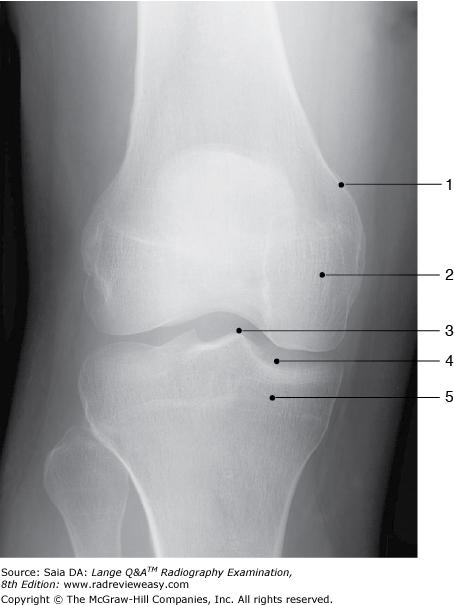

C fibula.

-The distal femur is associated with two large condyles; the deep depression separating them is the intercondyloid fossa (Fig. A). The proximal tibia has two condyles; their superior surfaces are smooth, forming the tibial plateau. The mandible has a condyle that articulates with the mandibular fossa of the temporal bone, forming the temporomandibular joint. The fibula has a proximal styloid process and a distal malleolus, but no condyle.